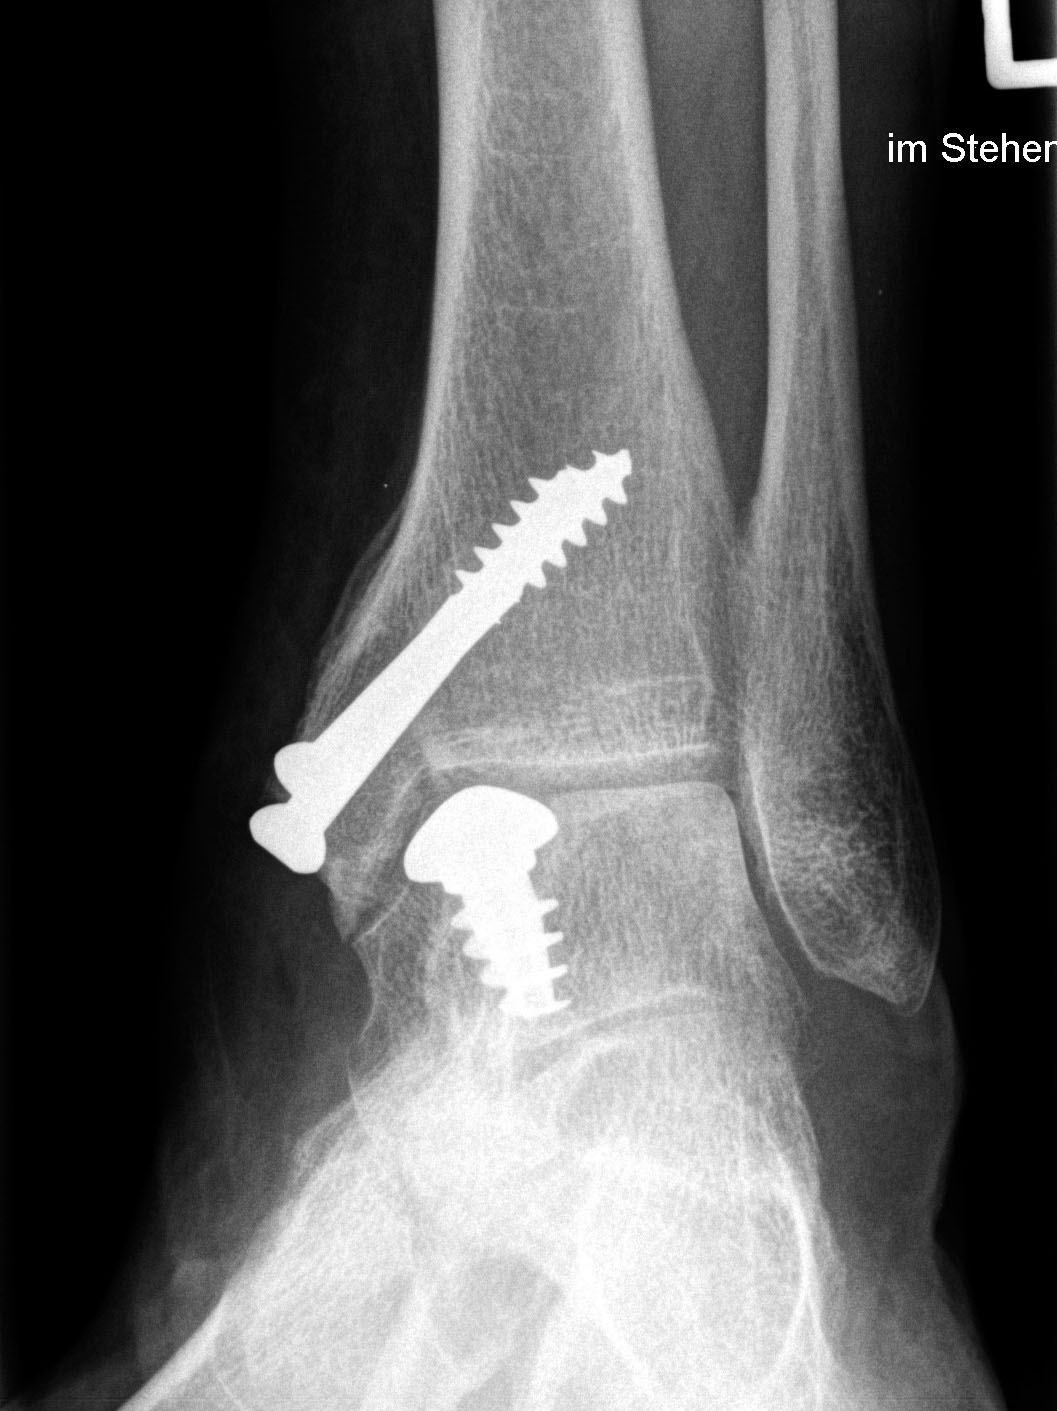

CAVE: Bei der postoperativen Röntgenkontrolle muss bedacht werden, dass die Knorpelschicht nicht abgebildet ist. Da das Implantat bei einer korrekten Positionierung unterhalb des Knorpelniveaus die knöcherne Fläche dennoch etwas überragt, kann dies zu einer Fehlinterpretation führen, dass das Implantat übersteht.

Zum Lesen der Bildbeschreibung und zur Vollansicht bitte die Bilder anklicken. Bilder: Sarah Ettinger.